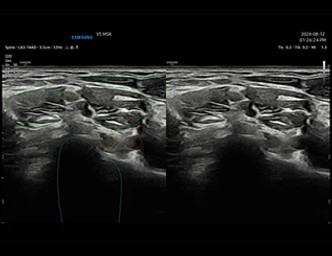

Derin öğrenme teknolojisini kullanarak sinirlerin yerlerini gerçek zamanlı olarak otomatik olarak algılar ve vurgular.